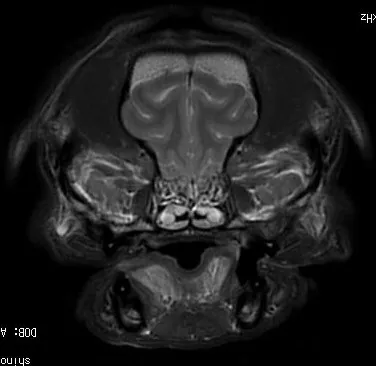

・MRI検査 など

各種検査でけいれん発作を起こすような異常や脳の構造や神経の異常がみられた場合は、その疾患に対する治療を行います。